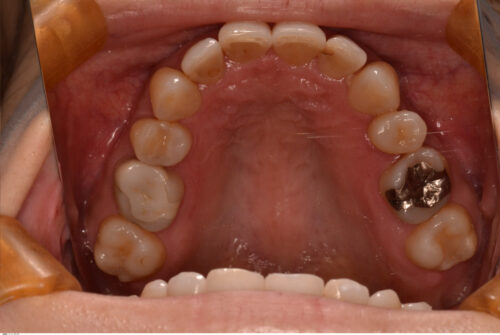

40代女性、主訴は噛み合わせを治したい。20年くらい前から頭痛に悩まされており、噛み合わせとの関連性もゼロとは言い切れません。

右上2番と左上3番が反対咬合のため、下顎のスムーズな側方運動が阻害されています。

第2小臼歯は全て先天性欠損で下顎にはブリッジが入っています。